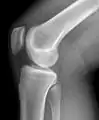

Рентгенограмма коленного сустава в боковой проекции.

Рентгенологическое исследование коленных суставов

Самым доступным, одним из информативных и распространённых исследований является рентгенологическое исследование.

Стандартные проекции, применяемые при рентгенографии коленного сустава — прямая (передне-задняя) и боковая. По мере необходимости их дополняют правой или левой косой, а также аксиальной проекциями. Основным правилом при рентгенологическом исследовании коленного сустава является полипозиционность[2][3].

На рентгенограммах между суставными поверхностями костей видна так называемая рентгеновская суставная щель. Рентгеновской она называется потому, что, будучи заполненной хрящом и прослойкой синовиальной жидкости, которые не дают изображения на рентгенограммах, она имеет вид более прозрачной полосы между суставными поверхностями.

Снимок, выполненный в положении максимального разгибания колена, является стандартным для передне-задней проекции. Он позволяет исследовать переднюю часть суставной щели. Прямой снимок коленного сустава может производиться как в положении лёжа, так и стоя. Когда суставная патология имеет механическую природу и предполагается повреждение связочного аппарата — предпочтительно производить рентгенографию стоя, как при нагрузке, так и в расслабленном состоянии, для исследования суставной щели и оси сустава.

Рентгенологическое исследование коленного сустава в прямой проекции обязательно дополняется боковым снимком. При боковой рентгенографии центральный луч проходит по суставной щели с уклоном на 10° в каудо-краниальном направлении. При этом края мыщелков бедренной кости накладываются друг на друга и их суставные поверхности смещаются в своей задней нижней части. Это позволяет хорошо различать их контуры и оценить состояние бедренно-надколенникового сочленения.

Боковой снимок коленного сустава производится либо в положении пациента лёжа на боку, в условиях полной расслабленности сустава, либо стоя, без нагрузки на исследуемый сустав. Лёгкое сгибание колена, равное 30° или 15°, позволяет определить состояние бедренно-надколенникового сочленения. Сгибание предназначено для визуализации надколенника в момент его внедрения в межмыщелковое пространство (трохлею).